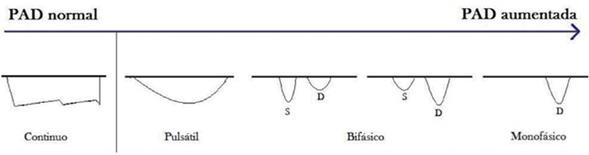

Flujo renal: se está investigando la evaluación de la PAD por Doppler del flujo renal en la insuficiencia cardíaca. Tang y colaboradores demostraron que la congestión venosa, con presiones derechas elevadas, altera el patrón de flujo venoso renal (normalmente continuo), haciéndolo pulsátil (discontinuo)23. El aumento de la PAD puede, entonces, manifestarse como un patrón bifásico durante cada ciclo cardíaco o por una disminución de la velocidad sistólica que evoluciona a un patrón monofásico diastólico, como se observa en la (figura 1)23. Los distintos patrones de flujo venoso renal se asocian pues con distintos niveles de PAD24.